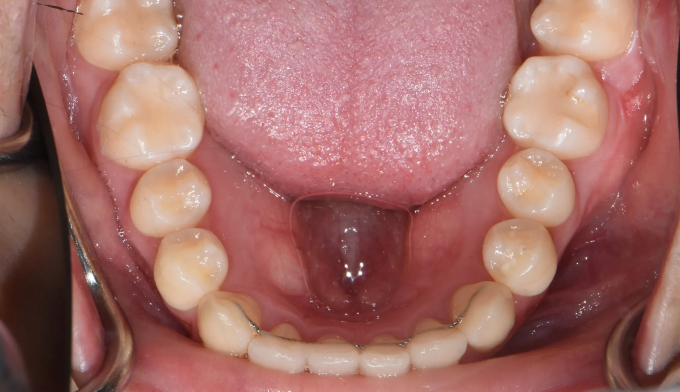

최대한 좁은 악궁을 확장하고 부족하면 전체 치열의 후방이동을 통하여 덧니를 배열할 공간을 만들었습니다.

총 치료기간은 25개월 입니다.

입술의 두께나 입매의 변화 없이 치열만 고르게 배열하였습니다.

치열과 안모를 동시에 고려한 교정치료가 꼭 필요합니다.